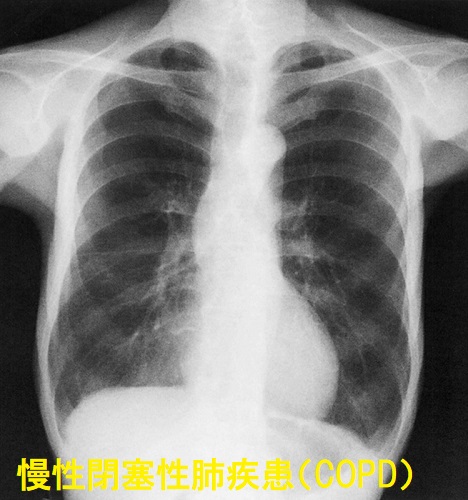

慢性閉塞性肺疾患(COPD)は慢性気管支炎や肺気腫の総称、タバコ等の有害物質を長期間吸入で起こる。COPD患者は特に女性で甲状腺の病気が多い。中枢性甲状腺機能低下症は特に多く重症COPDほど合併率が高い。甲状腺機能亢進症/バセドウ病では甲状腺ホルモンの交感神経刺激作用で気管支拡張しCOPDがマスクされ、治療後、元に戻りCOPD出現/再発/増悪。逆の報告として甲状腺ホルモンの異化亢進により呼吸筋力低下、呼吸機能が悪化。COPDが重症な程、低酸素症も重篤(重症)で異化亢進を抑える低T3症候群(ノンサイロイダルイルネス)の頻度が高い。

慢性閉塞性肺疾患(COPD:chronic obstructive pulmonary disease)は、慢性気管支炎や肺気腫の総称です。タバコ等の有害物質を長期間吸入すると、

- 気管支の炎症(慢性気管支炎)

- 酸素交換の場である肺胞が破壊(肺気腫)

に至ります。90%以上はタバコが原因で、タバコによる肺の生活習慣病(別名「タバコ病」)です。

40歳以上の10人に1人は慢性閉塞性肺疾患(COPD)の疑いがあるとされ、めずらしい病気ではありません。世界の死亡原因の第4位を占め、放置すると命にかかわります。

肺気腫では

- CO肺拡散能(DLco)低下

- 肺がのび切ったゴムのようになり(肺コンプライアンス上昇)、速く息を吐けなくなる。呼気時間は延長し、最大呼気流速が減るため、フローボリューム曲線の下行脚は上に凹

- II型呼吸不全;PaCO2 上昇、PaO2 60 Torr 以下